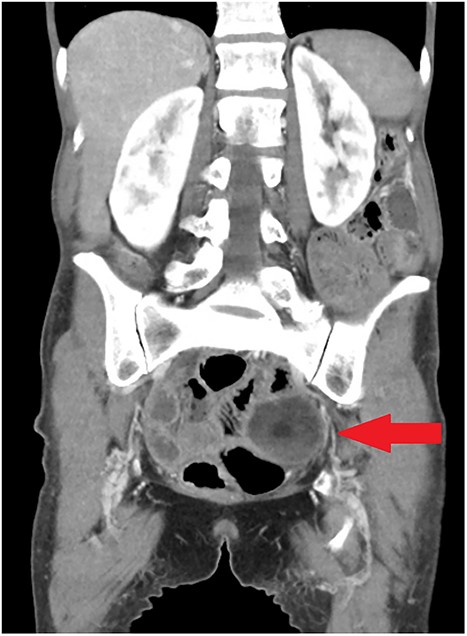

On examination she had a diffusely tender abdomen, with maximal tenderness in her left lower quadrant. Her neutrophils were 16x109/L and C reactive protein 98 mg/L. Computed tomography (CT) imaging of the abdomen and pelvis demonstrated patchy mucosal enhancement of the right colon in addition to a complex left-sided dermoid cyst (Fig. 1), which was confirmed on pelvic ultrasound.

Coronal view of initial CT scan demonstrating left adnexal dermoid cyst (arrow).